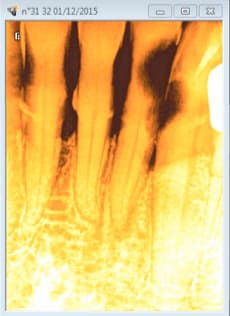

Exemple .

Radio de diagnostic le 01 12 2015, 32 à dévitaliser.

Le patient :" Ah non j'ai pas mal"

Vu aujourd'hui en urgence. Pulpite si si si dent vivante-)

Radios per et finale ( cone en place et cone scellé) gratuites. -)

Crampons de digue sur 36 et 46. -)

Sinon pas eu de remarque sur les clamp sur la radio lime en place ou final, pourtant ça cache une bonne partie de la dent! (on reconnait l'escroc à l'utilisation de la digue sous laquelle il se cache pour commettre ses méfaits)